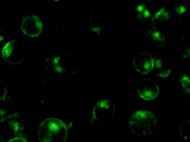

Natural Killer Cells commonly referred to as NK Cells are a type of innate lymphocyte which aid the immune system by killing virally infected cells and controlling signs...